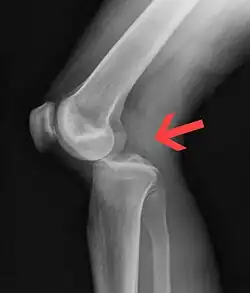

| Plain lateral X-ray of the left knee showing a posterior knee dislocation[1] | |

Plain X-rays, CT scan, ultrasonography, or MRI may help with the diagnosis.[2][11] Findings on X-ray that may be useful among those who have already reduced include a variable joint space, subluxation of the joint, or a Segond fracture.[5]

They may be divided into five types: anterior, posterior, lateral, medial, and rotatory.[4] This classification is based on the movement of the tibia with respect to the femur.[11] Anterior dislocations, followed by posterior, are the most common.[2] They may also be classified on the basis of which ligaments are injured.[2]